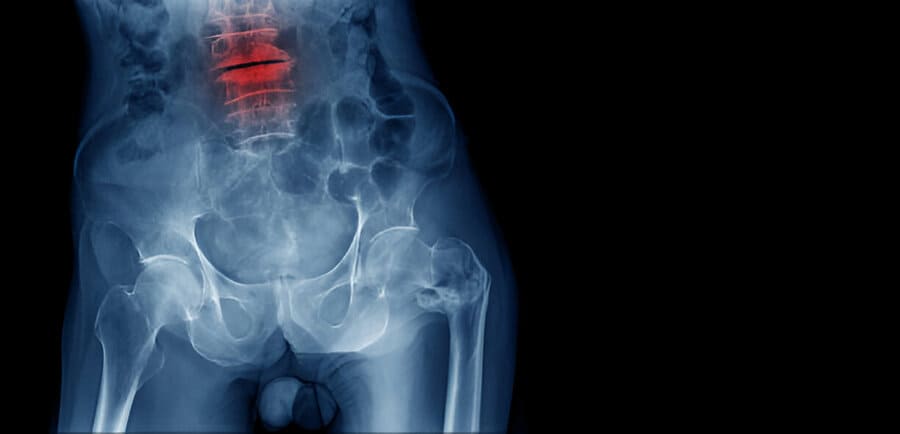

Understanding the Significance of a C2 Fracture for the Spine

A C2 fracture affects the second cervical vertebra, crucial for supporting the skull and enabling neck movement. When a fracture occurs in this vertebra, it can no longer maintain proper alignment or safeguard the spinal cord effectively.

This condition may lead to symptoms such as severe pain, limited mobility, and potentially neurological impairments. Therefore, it is crucial to seek immediate medical evaluation to assess the extent of the injury and determine the most appropriate treatment options. C2 fractures can result in both immediate and long-term complications, but with prompt medical attention, the risks can be minimized and recovery facilitated.

If proper stabilization is not achieved, the vertebrae may become misaligned, raising the risk of permanent spinal cord injury or paralysis. Addressing these fractures promptly is essential to minimize risks and facilitate recovery.